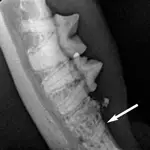

Step 1

Intraoral radiograph of #407 shows a clearly defined intact mesial root (arrow) and ill-defined distal root with type 2 resorption. The clinical lesion of gingivitis is noted over the retained mesial root.